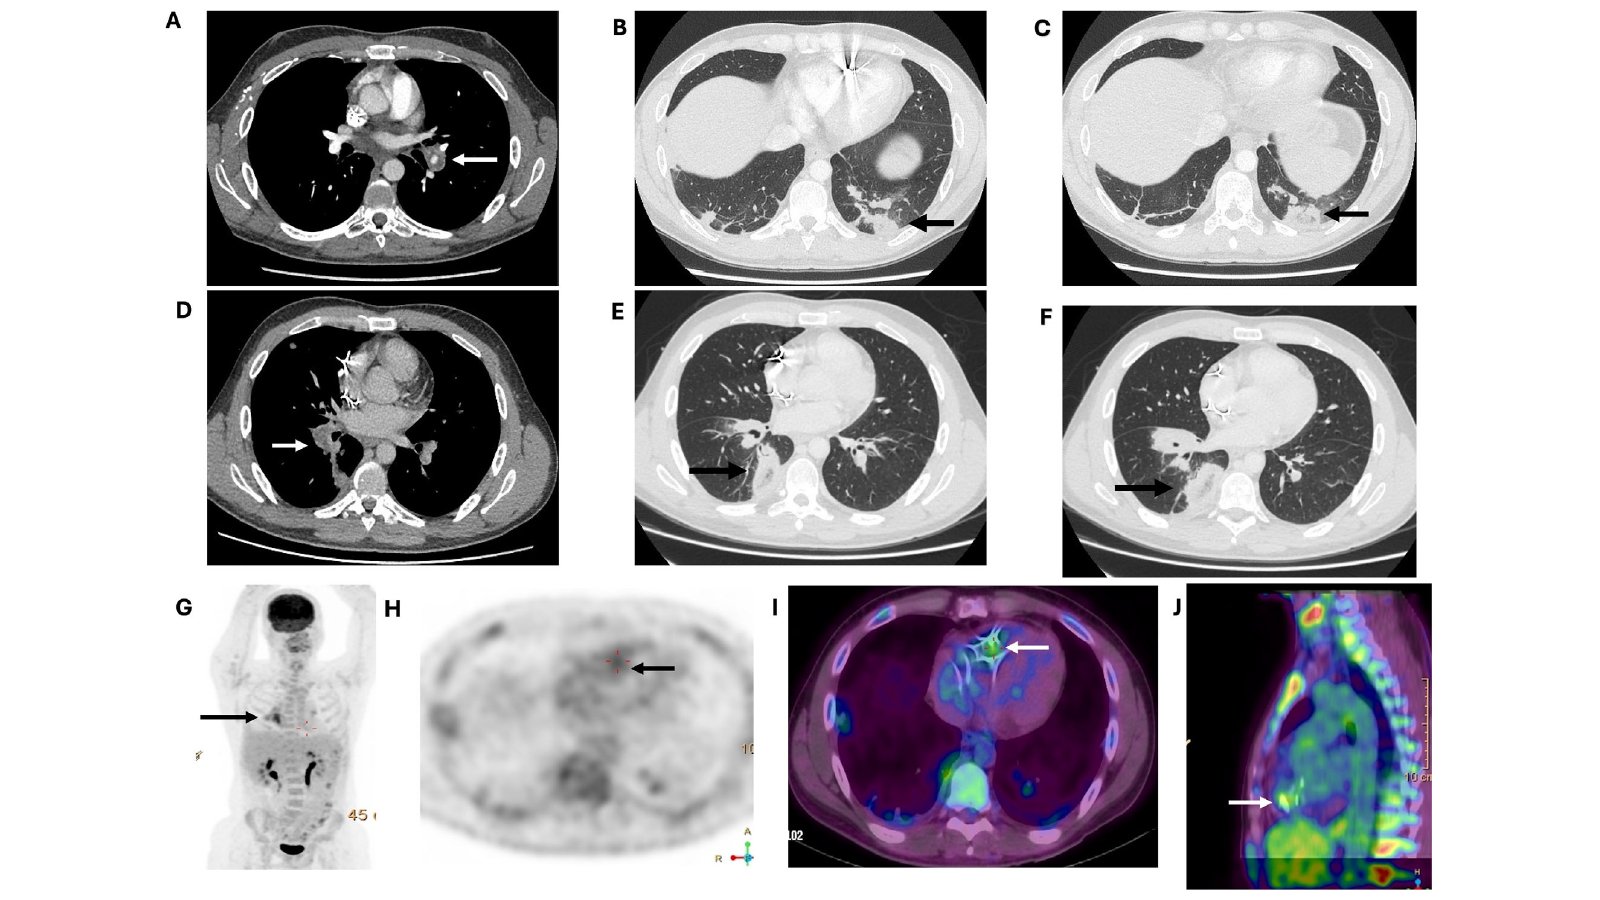

Advanced imaging eventually showed focal radiotracer…